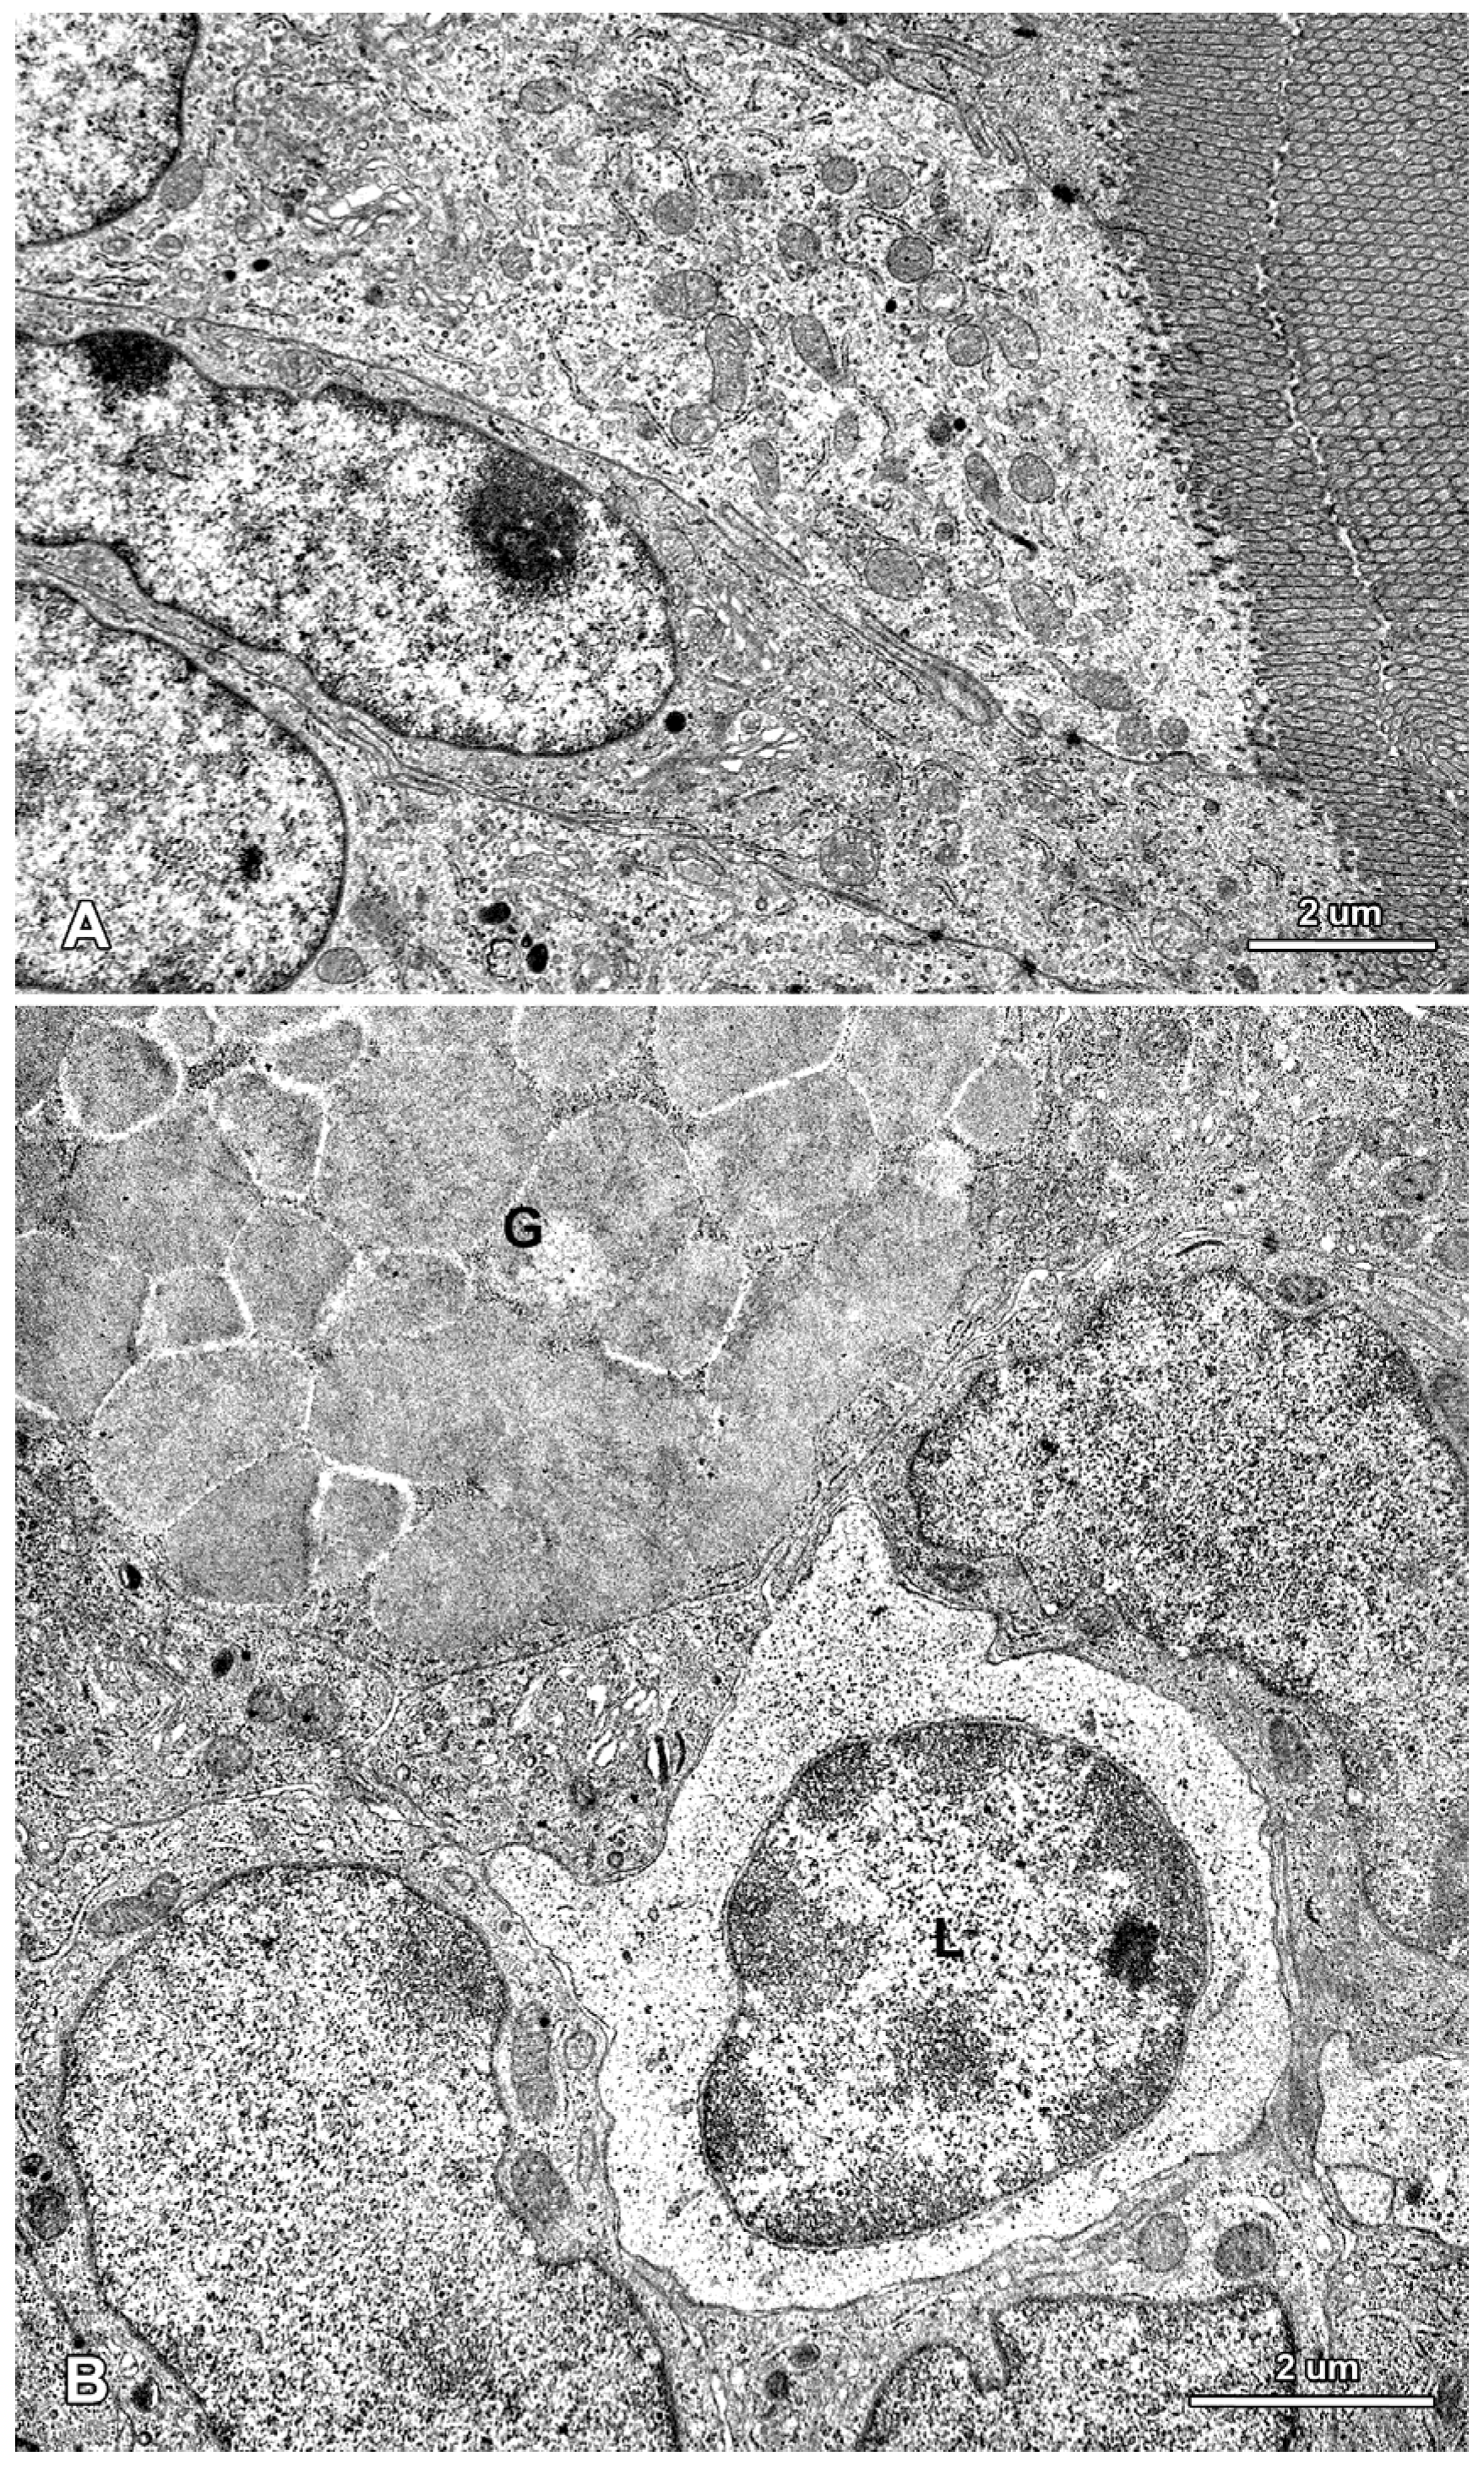

In the control pigs, the epithelium covering villi and forming crypts showed a typical organization in samples taken after one, three, and six weeks of the experiment. The absorptive cells were the major epithelial component and showed the polarity of cellular organization (Figure 5A). These cells were tall and columnar with a basally situated, oval nucleus. The basal part of the cytoplasm contained a few mitochondria and profiles of rough and smooth endoplasmic reticulum. In the apical part of the cytoplasm many mitochondria, elements of the endoplasmic reticulum, and microtubules were observed. The Golgi apparatus was located close to the nucleus. The apical surface formed well-developed microvilli. The adjoining cell membranes of the absorptive cells were close to each other, and the junctional complexes were well-formed. The goblet cells were interspersed among the absorptive cells and had a typical ultrastructure (Figure 5B). Lymphocytes were present between the epithelial cells (Figure 5B).

Ultrastructure of the jejunal mucosa epithelium in a control pig after six weeks of the experiment. (A) Enterocytes with a characteristic structure of the apical part; (B) An intraepithelial lymphocyte (L) and a fragment of a goblet cell (G).